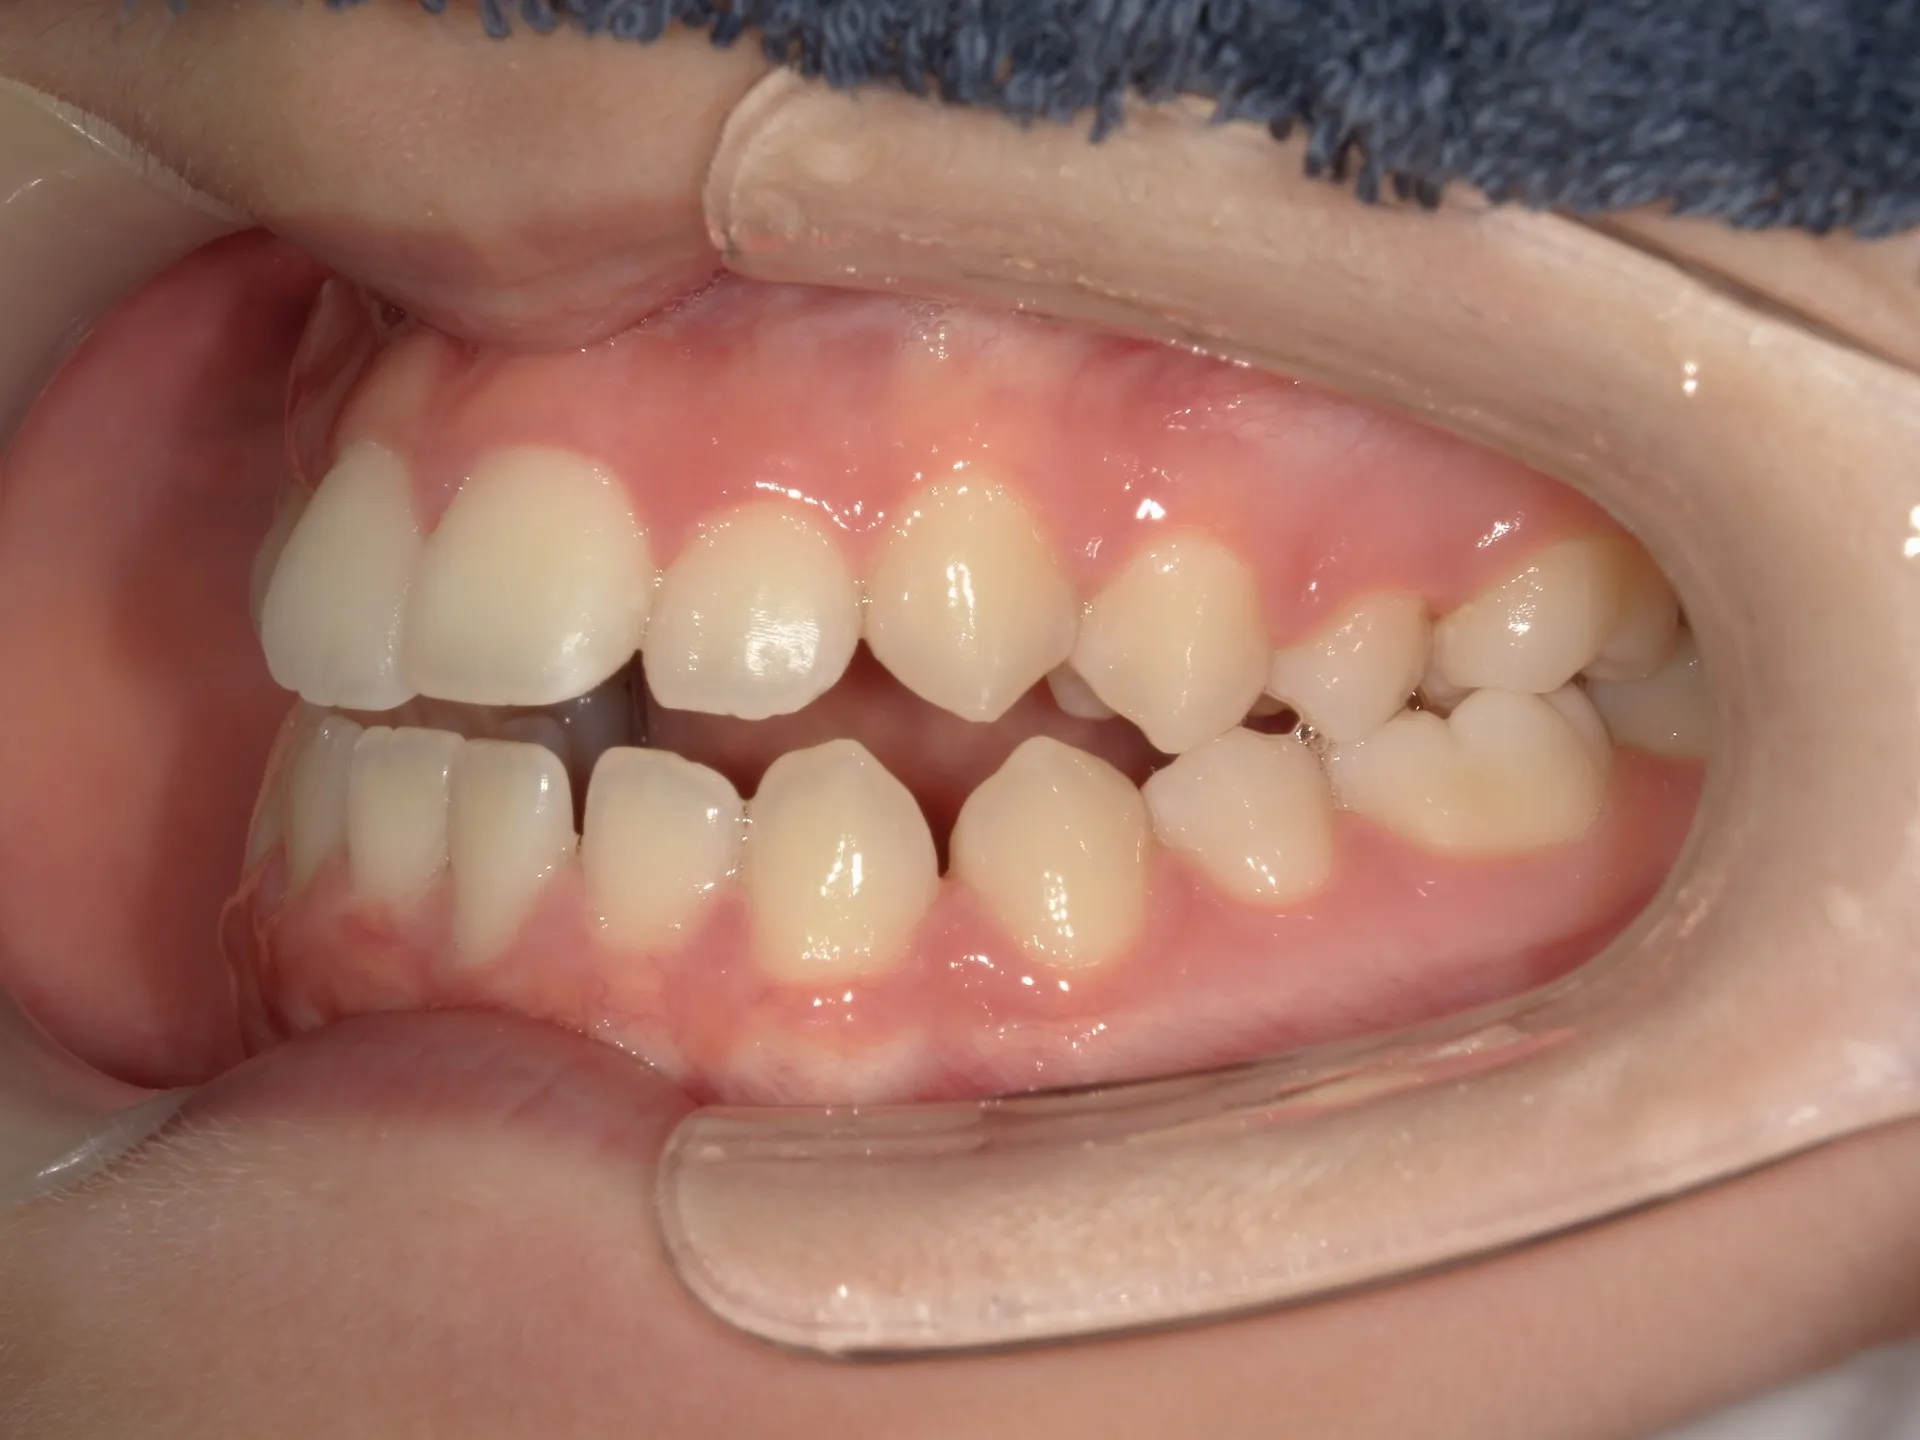

開咬治療後

治療後の正面観ですが、最初に見えていたスペースは大きく減少していることが分かりますが、左側にはややスペースは残存している状態です。

矯正治療では歯医者が目指すゴールと患者様が考えているゴールはしばしば異なることがあります。

今回は歯医者目線でお話するともう少し矯正を続けた方がよりきれいに機能的になると考えるため矯正治療の続行を提案したいところではあります。

しかしながら、マウスピース矯正で一番大事なことは患者様のモチベーションです。

患者様はこれだけ歯並びが治っているのでもう続ける必要性を実感しないため、マウスピース矯正の煩わしさをまだ続けないといけないのかと嫌になってしまいます。